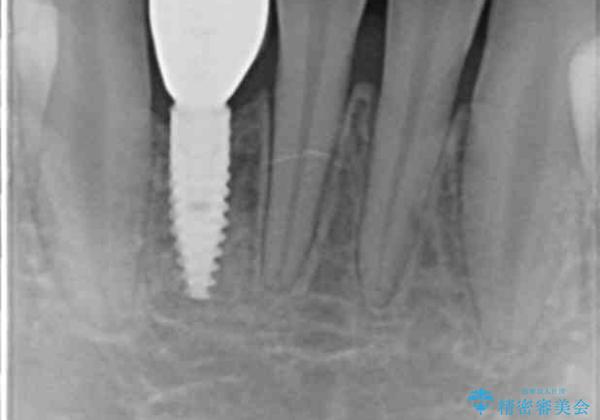

[ 先天性の前歯欠損 ] 矯正とインプラントの包括治療

- 「全体的な歯並びの矯正治療、もともと前歯がないところに歯を入れたい。」、と総合的な治療を希望され来院されました。

マウスピース矯正インビザラインで全体の歯列矯正を行うと同時に、前歯の欠損部位もインプラントを埋入するのに十分なスペースを確保し、インプラントの埋入手術を行います。

- 55万円(仮歯・ストローマンインプラント・アバットメント・ジルコニアクラウン・骨造成)費用は治療当時の料金となります